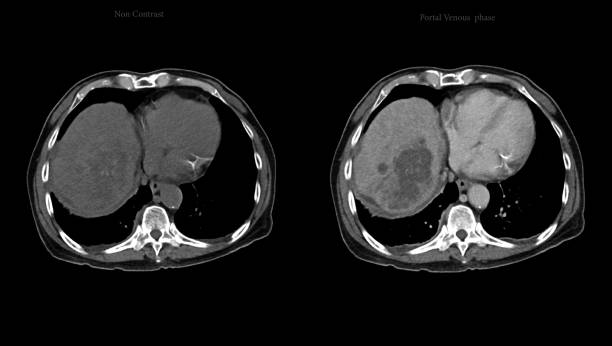

게실염은 대장의 벽에서 바깥쪽으로 튀어나온 주머니 형태의 작은 부어오르는 현상을 말합니다.

이 주머니 형태는 대장 벽의 약한 부위에서 발생할 수 있으며, 오른쪽 대장이나 왼쪽 대장에서 발생할 수 있습니다.

게실염은 주로 복통을 유발하며, 위치에 따라 우측 대장 게실염과 좌측 대장 게실염으로 나눌 수 있습니다.

게실염은 서양에서는 좌측 대장 게실염이 흔하게 발병하지만, 한국에서는 우측 대장 게실염이 더 흔하게 나타나는 편입니다.